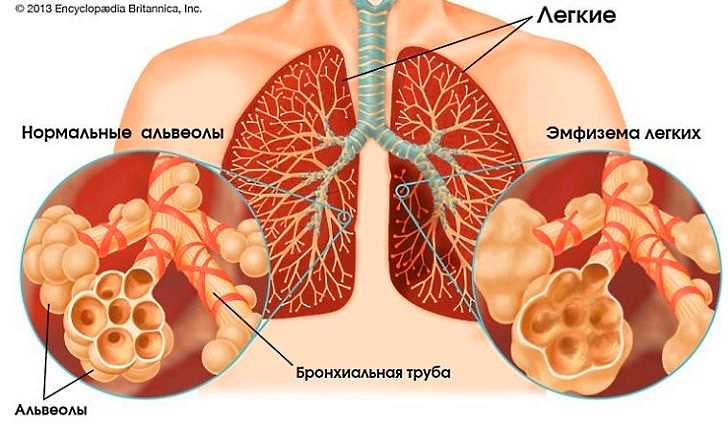

В структуре легких есть альвеолы – воздушные пузырьки, обеспечивающие процесс дыхания. В здоровых легких альвеолы при наполнении кислородом увеличиваются, во время выдоха – уменьшаются до анатомических размеров. Если эти воздушные пузырьки поражаются каким-то заболеванием, это состояние характеризуется как эмфизема легких.

Эмфизема – патология легких, когда расширение альвеол происходит до чрезмерных размеров, от чего начинается деструкция тканей. Она заключается в истончении стенок альвеол, потере их эластичности, нарушении способности к нормальным сокращениям, деструктивно-морфологических изменениях альвеолярных стенок. Это происходит от воздействия большого давления.

Эмфизема лёгких – что это такое, ее симптомы, лечение хорошо знают врачи-пульмонологи, занимающиеся патологиями легких, их изучением, разработкой терапевтических методик. Легочные ткани поражаются патологической деструкцией, образуются пустоты с воздухом, из-за которых легкие увеличиваются в размерах. Эмфизема разрушает перегородки между альвеолами, нарушает дыхание.

Пациент вдыхает воздух в нужном количестве, а выдох сделать не может, увеличенные полости пораженных альвеол не справляются со своими функциями. В результате воздух накапливается внутри легких, они увеличиваются, доходят до 15 см. Развивается недостаток дыхания, начинается эмфизема лёгких. Что это такое, по симптомам сам заболевающий человек определить не может, тем более не может выбрать для себя лечение. Это должен делать только квалифицированный специалист.